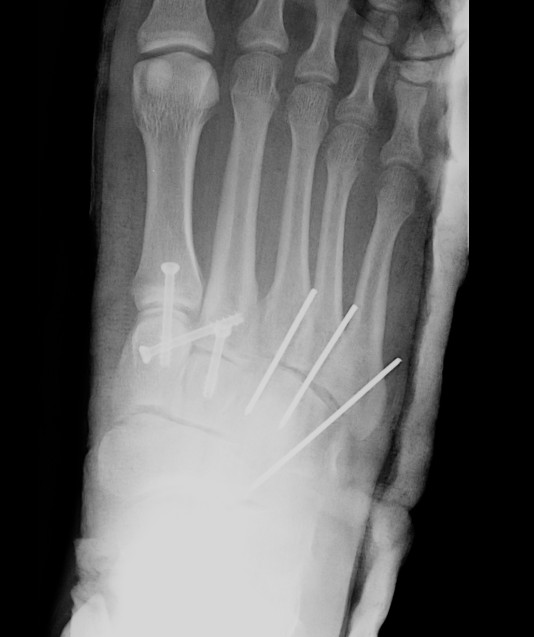

Screw fixation 1st and 2nd TMT with K wire fixation 3rd / 4th / 5th